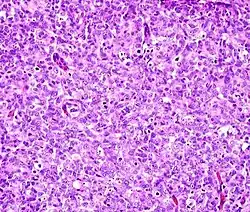

This can be done to slides processed by the chemical fixation or frozen section slides. To see the tissue under a microscope, the sections are stained with one or more pigments. The aim of staining is to reveal cellular components; counterstains are used to provide contrast.

The most commonly used stain in histology is a combination of hematoxylin and eosin (often abbreviated H&E). Hematoxylin is used to stain nuclei blue, while eosin stains the cytoplasm and the extracellular connective tissue matrix of most cells pink. There are hundreds of various other techniques which have been used to selectively stain cells. Other compounds used to color tissue sections include safranin, Oil Red O, congo red, silver salts and artificial dyes. Histochemistry refers to the science of using chemical reactions between laboratory chemicals and components within tissue. A commonly performed histochemical technique is the Perls' Prussian blue reaction, used to demonstrate iron deposits in diseases like Hemochromatosis.[2]